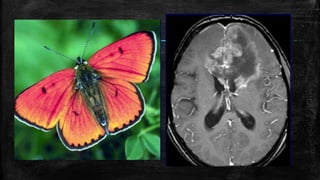

Hot cross bun sign-MSP

• #105 Hot cross bun sign. Axial T2W MRI image of the pons (A) in a patient with multiple system atrophy shows a hyperintense linear area forming a ‘cross’ (arrow) in the pons. Sagittal T1W image (B) shows atrophy of the cerebellum and cerebrum (prominence of sulci)